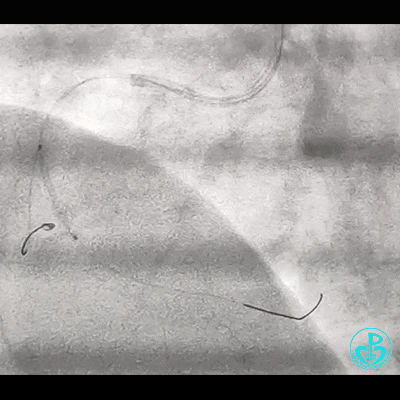

右锁骨下动脉迂曲打圈,影像如下:

导丝怎么扩右冠近段弥漫性病变中远段闭塞顺利开通并植入支架,哪知道故事才刚刚开始!!!_https://www.jmylbn.com_新闻资讯_第1张

导丝怎么扩右冠近段弥漫性病变中远段闭塞顺利开通并植入支架,哪知道故事才刚刚开始!!!_https://www.jmylbn.com_新闻资讯_第2张